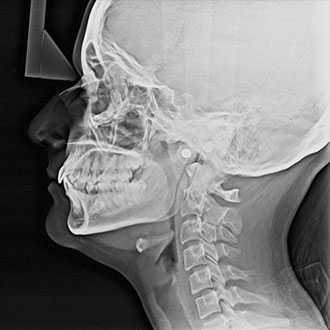

Cephalometric radiography provides a complete view of the dento-maxillo facial region. The functionally designed and easy to use head positioner ensures accurate patient positioning in lateral a.p and p.a technique.

Diagnostic Tests / Digital OPG. ... An Orthopantomogram (OPG), also known as an "orthopantogram" or "panorex", is a panoramic scanning dental X-ray of the upper and lower jaw. It shows a three-dimensional view of a half-circle from ear to ear.